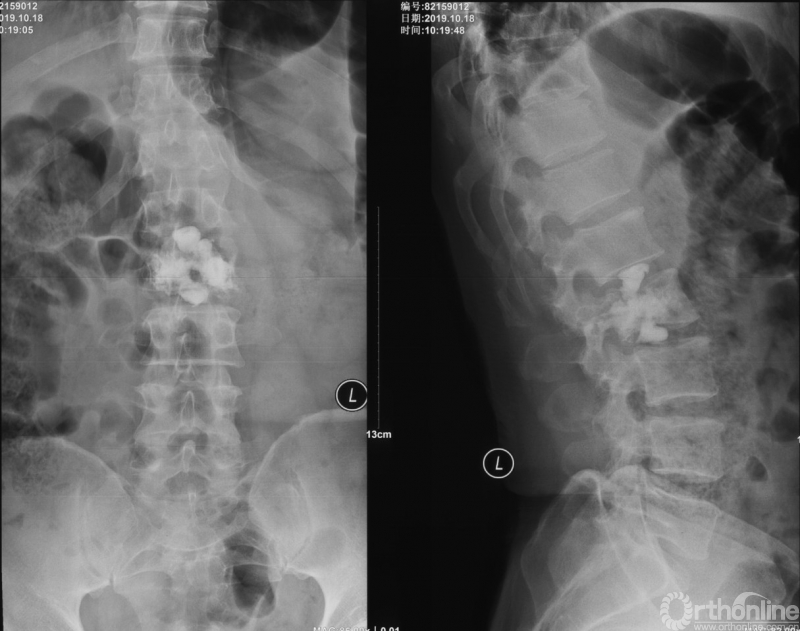

PVP治疗

术后6个月

为进一步减少创伤,获得更好的综合疗效。骨采用经皮内固定的微创杂交技术,暨经皮内固定结合小切口分离手术,手术失血900ml,术后7天出院。

术中资料